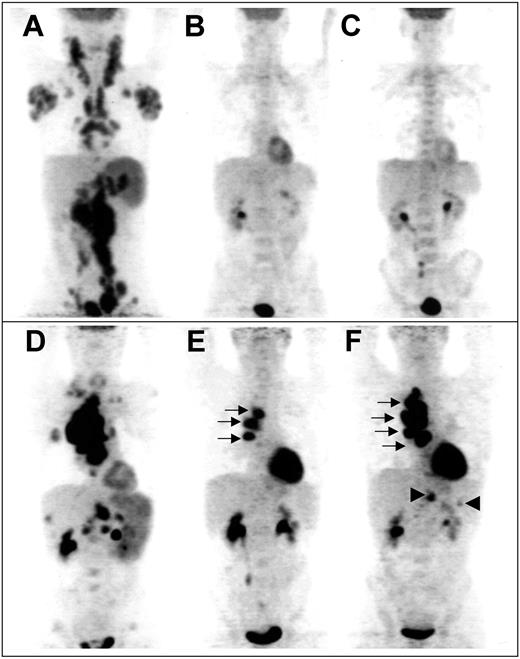

“Late PET” data were available in 80 patients. The reasons 10 patients were not explored at 4 cycles were 2 toxic deaths during the induction phase, one early withdrawal after 2 cycles due to aspergillosis, 3 disease progressions, and technical problems in 4 patients. Sixty patients were considered “late PET” negative after 4 cycles, among whom 52 were in CR on the basis of CDMs (case example in Figure 2A-C). Forty-seven of these 60 patients were previously “early PET” negative, whereas 13 patients who were initially “early PET” positive converted into “late PET” negative. The 2-year event-free survival and overall survival of these 13 patients were 85% and 83%, respectively. It is noteworthy that none of the “early PET”-negative patients became positive after 4 cycles. In addition, 20 of the 33 “early PET”-positive patients who were analyzed after 4 cycles remained positive (case example in Figure 2D-F); 9 of these patients were considered in CR on the basis of CDMs but 3 of them had relapses after 4, 11, and 12 months, respectively.

Example of sequential FDG-PET findings in 2 patients. Panels A-C show scans from a patient with truly negative “early PET,” predicting CR. (A) Pretherapeutic scan shows diffuse involvement of jugular chains, axillae, mediastinum, mesenteric chains, spleen, and lateroaortic and iliac chains. No residual uptake is seen after 2 cycles (B) and after 4 cycles (C) of chemotherapy, whereas a medullar uptake is evidenced, due to hematopoietic activation. Panels D-F show scans from a patient with truly positive “early PET,” predicting relapse. (D) Pretherapeutic scan shows a cluster of hypermetabolic nodes in the right pulmonary hilum, supraclavicular and mesenteric nodes, and involvement of the spleen, right lung, liver, and lumbar spine. Three hilar foci persist after 2 cycles (E, arrows); their extent increases after 4 cycles (F, arrows), whereas subdiaphragmatic sites reappear (arrowheads), indicating progression of the disease.